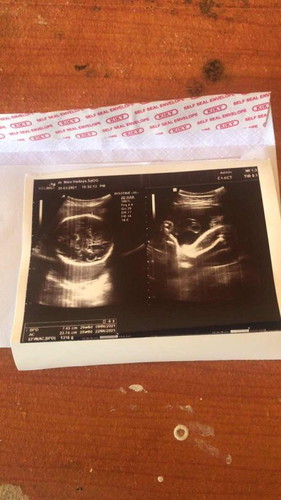

Hasil USG , Kmrin di UsG katanya anak ku kelilit tali pusar,tapi aku brhrap lahiran normal minta doanya ya bunda” 😢🙏🙏

Semoga persalinan lancar tinggal hitung hari HPL 15 juni